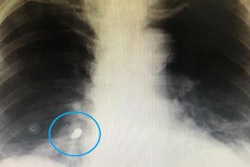

First, a chest x-ray was completed, which showed a 2-cm metallic foreign body within the patient's right airway. The object was consistent with a dental drill head that had been aspirated, the authors wrote.

Figure 1: Posteroanterior chest x-ray. A metallic foreign body (the drill head) is visible near the right hilum, supposedly located in the right airways. Images and captions courtesy of De Chiara et al. Licensed under CC BY-NC-ND 4.0.